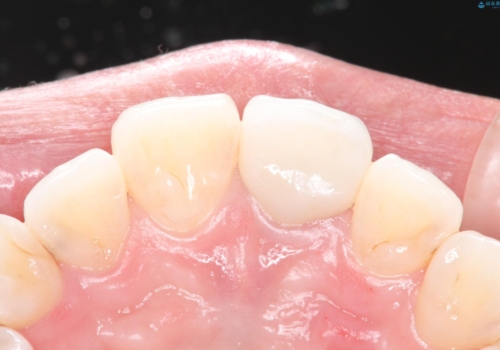

- 28.6万円(内訳:根管治療11万円、土台2.2万円、仮歯1.1万円、オールセラミック[スペシャル]14.3万円)費用は治療当時の料金となります

色や形など自然な仕上がりにご満足いただけました。